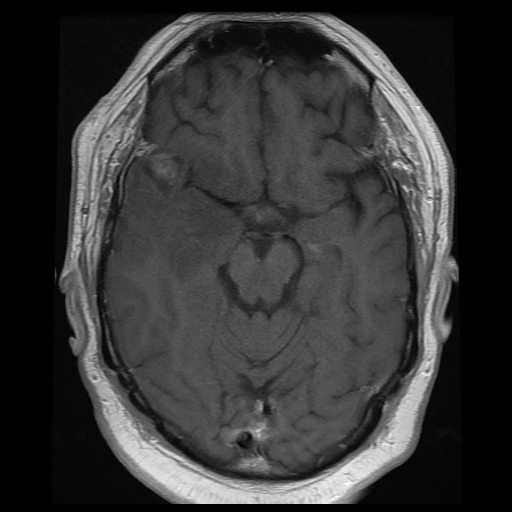

Clinical information: The patient was a 76 year-old man with a history of Parkinson's disease. He developed sudden onset weakness of lower extremities while standing. He did not fall and was able to sit down. There was a brief tremor of his upper extremities but there was no seizure. On furhter work up, an enhancing mass, 2.0 x 1.6 cm, was noted in his right temporal pole. The mass was resected.

Radiology of the Case: The mass is located at the tip of the right temporal lobe causing minimal midline shift. There is heterogensous enhancement suggestive of necrosis (Panel A). There is substantial edema around this mass with extension inot the posterior temporal lobe, insula, and inferior lateral frontal lobe (Panel B). The edematous area on FLAIR probably